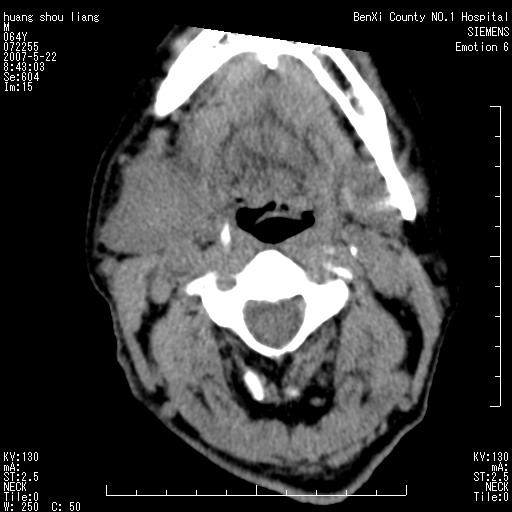

男性,64岁。颈部包块8年。最近增大。

对不起大家,可能是片子发太多有点乱,正常腮腺在下颌角的外侧,颌下腺在下颌体的中部内侧,本例在下颌角内侧偏下,和腺体一点关系都没有,从vrt和mpr上可以很明显看出来,再者肿块是好多粘连在一块的,大家在仔细看看,左侧可能也是吧,我还是考虑为肿大的淋巴结融合在一块,但性质??????

右侧腮腺下部均匀软组织密度肿块,外形不规则,与周围组织分界清晰,考虑右侧腮腺混合瘤或多形性腺瘤。

颈部肿块好像有三个';';7';';字规律,7天多考虑急性炎症,7周多考虑新生物,7年多考虑先天性病变,这个病历还是增强吧

大家好,病理结果出来了,如大家所说,颌下腺混合瘤。

唉,解剖没学好吧,我诊断错了,不过还是有些不理解回去我在多看看书,谢谢大家的参与,以后我还会奉献好的病例。